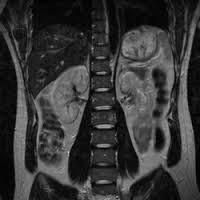

接下来就是磁共振,磁共振的远离简单的说:正常情况下人体内的氢原子核处于无规律的进动状态,当人体进入强大均匀的磁体空间内,在外加静磁场作用下原来杂乱无章的氢原子核一齐按外磁场方向排列并继续进动,当立即停止外加磁场磁力后,人体内的氢原子将在相同组织相同时间下回到原状态;这称为驰豫,而病理状态下的人体组织驰豫时间不同,通过计算机系统采集这些信号经数字重建技术转换成图像就可以给临床和研究提供科学的诊断结果。

磁共振和CT的区别主要在于成像的性质,CT是根据组织的密度,由于人体不同组织的密度不同,来发现病灶;而磁共振是判断不同加权所产生的不同信号。磁共振于对软组织滑膜、血管、神经、肌肉、肌腱、韧带、和透明软骨的分辨率高。由于其特殊的性质,磁共振看骨头不行,而在大脑的检查中则有着不可替代的作用。

在这里还要顺便提一下,磁共振扫描的时间相对CT会更长,但是并没有辐射,相对安全。还要说一句的是磁共振仪器是一个巨大的磁场,进去磁共振室一定要卸下随身携带的金属物品,不然都会被吸到机器上。曾今也有许多案例和教训,比如患者的输液架被仅仅吸住,所有人都拉不开,不得不叫来大型工程设备;还有患者要求将轮椅推入,医生拼命阻止,患者不理解,最后造成严重纠纷。